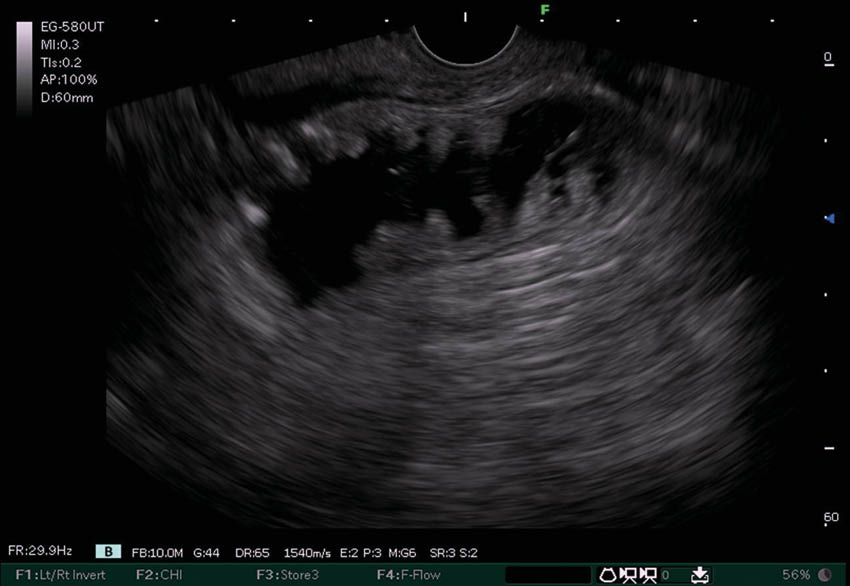

Schritt 1: Mittels Endosonographie wird eine

Jejunalschlinge vom Magen aus dargestellt. Die anatomische Nähe ist die Grundvoraussetzung für eine erfolgreiche EUS-GE.

Schritt 2: Unter endoskopischer Sicht wird ein Führungsdraht durch die Stenose vorgeschoben und darüber eine Sonde in die Zielschlinge gelegt. Die Jejunalschlinge wird mit Flüssigkeit und Indigokarmin aufgefüllt. Die Flüssigkeit wird benutzt um die Jejunalschlinge zu entfalten und eine sichere Punktion zu ermöglichen. Das Indigokarmin wirkt später als Beweis, dass der Stent in die richtige Jejunalschlinge appliziert wurde.